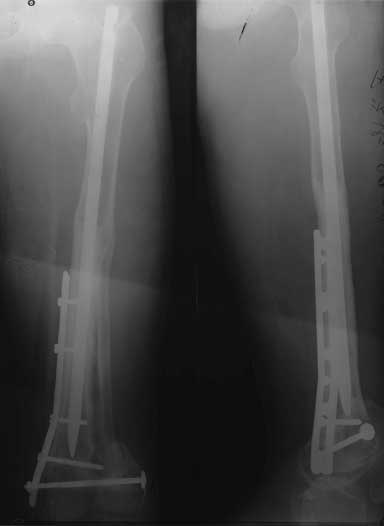

肱骨远端骨缺损,三次手术

13厘米异体骨                               13厘米异体骨,加钢板固定

术后1年,骨折愈